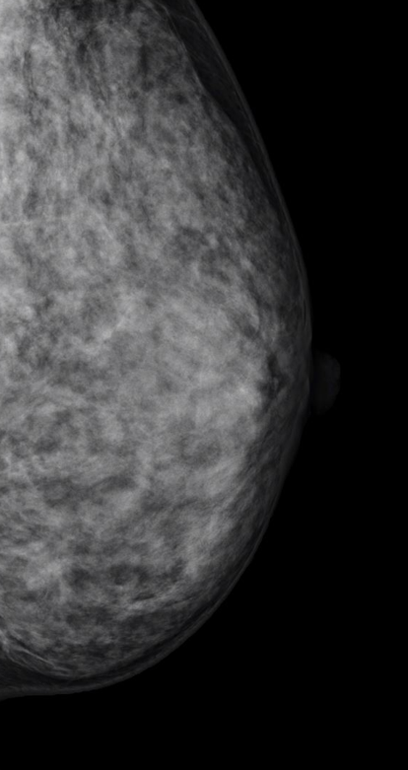

乳房トモシンセシスについて

トモシンセシス撮影とは、マンモグラフィの 3D 画像のことです。従来のマンモグラフィと同様に、乳房を挟んだ状態で複数の方向から撮影を行い、1mmスライスの細かい画像を作成します。通常のマンモグラフィに追加して撮影することで、乳腺の重なりによって発見しづらかった病変が見つけやすくなります。厚みのある乳房内の重なりを減らすことにより、乳腺の奥の病変の観察がしやすくなります。一回の圧迫時間は 10〜15 秒程度で、ぶれないように息を止めて撮影します。

2D撮影

トモシンセシス撮影